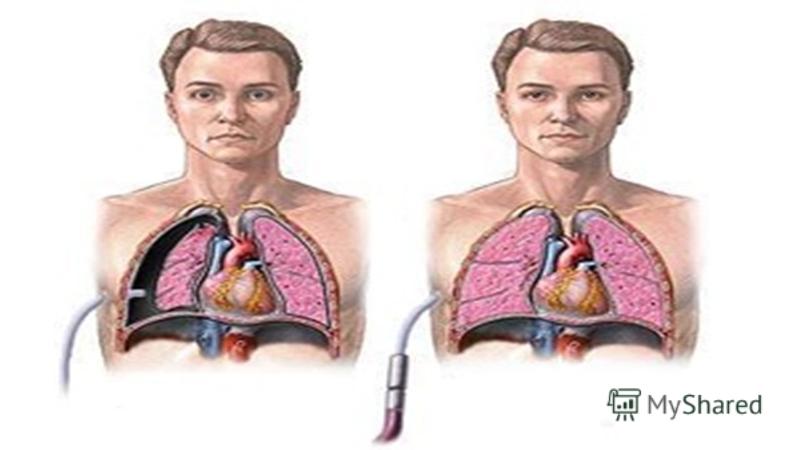

Схемы дыхания: Пневмоторакс на изображениях